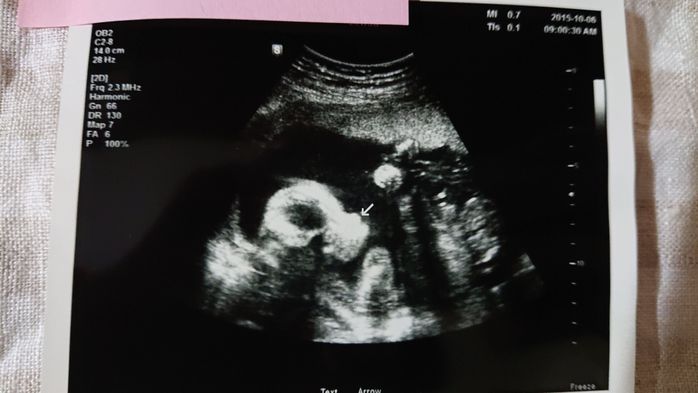

《妊娠30週目のエコー写真》

この写真を撮る2週間程前に切迫早産で入院してしまったのですが、入院してから初めて撮った30週目のエコー写真です。妊娠後期になってくると、赤ちゃんが大きくなりすぎて、ほんの一部しかエコー写真に写らなくなってきました。「赤ちゃんの顔が見たい」と思っても、この日は赤ちゃんの向きが合わずに見ることができませんでした。「赤ちゃんの向きによって、赤ちゃんの顔を見られずに終わってしまう時もある」と、医師に言われて、何だか残念に思ったものです。